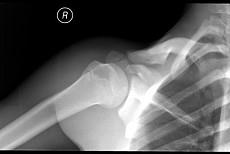

男,请根据其正常肩关节影像图像,判断其最可能的年龄 ( )A、36岁左右B、26岁左右C、46岁左右D、16岁左右E、56岁左右

问题 男,请根据其正常肩关节影像图像,判断其最可能的年龄 ( )

选项 A、36岁左右 B、26岁左右 C、46岁左右 D、16岁左右 E、56岁左右

答案 D